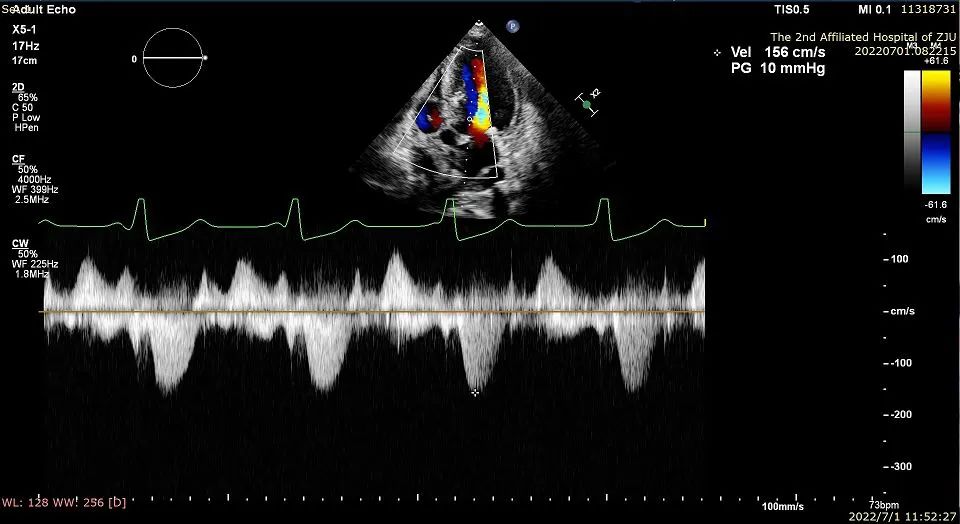

2022年7月1日在浙江大学医学院附属第二医院导管室,应用Liwen RF射频消融系统经心尖到达肥厚室间隔进行射频消融,术后即刻超声显示靶区消融充分,术后即可左室流出道压差显著降低。

患者为一名40岁的女性。超声提示患者室间隔最大厚度为31.3mm,静息压差为102mmHg,负荷状态下为146mmHg。二尖瓣呈SAM征伴有少量反流。

术后左室流出道压差